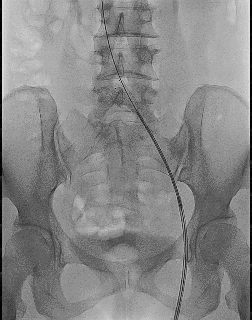

4、再次造影,支架形态良好,髂静脉狭窄解除,髂静脉回流较术前明显改善,髂内静脉返流消失,周围侧支减少。

此例患者在植入支架过程中,可以感受到几个优点:首先是释放过程中稳定性很好,大小滚轮可以有效控制支架的释放精度和速度,既能充分覆盖病变,也可以避免对对侧髂静脉开口的遮挡;其次支架开放形态良好,体现了其强支撑性;术后造影支架贴壁形态良好,而且术后患者不适感轻微,应该与支架的柔顺性相关。